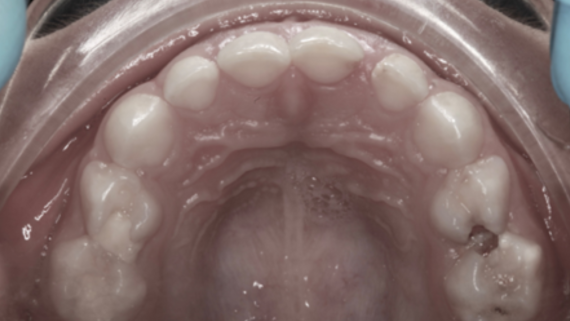

Este paciente acudió a Clínica Dental Urumea para mejorar la estética de su sonrisa. Primero se realizó un tratamiento de ortodoncia con alineadores transparentes Invisalign, para alinear y corregir la mordida cruzada.